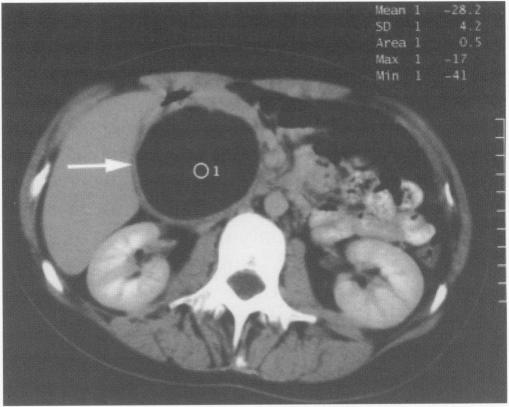

Acute presentation of lymphangioma of the retroperitoneum.

Ulster Med J. 2004 Nov;73(2):129-31.